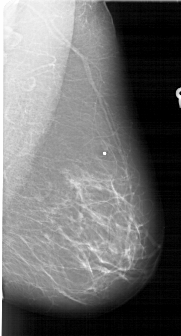

A_1687_1.RIGHT_CC

RIGHT_CC LINES 6466 PIXELS_PER_LINE 3511 BITS_PER_PIXEL 12 RESOLUTION 43.5 NON_OVERLAY